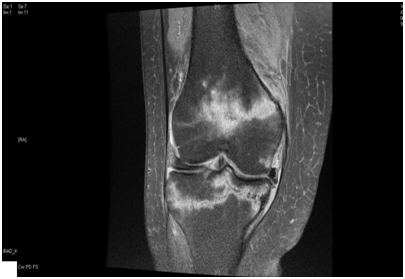

We present a 77 years old Caucasian female with spontaneous onset of pain in both knees for several weeks before presenting to the casualty then to our fracture clinic. There was no history of trauma. The patient is known to have Rheumatoid arthritis (RA) for over 30 years and has been on Bisphosphonate treatment (Alendronate) for over 24 months following the diagnosis of osteoporosis by DEXA scan. Plain radiographs showed subtle linear areas of sclerosis bilaterally in her proximal tibiae (Figure 1 & 2). Magnetic resonance imaging confirmed the presence of extra-articular linear high signal intensity change on T1, T2 with surrounding marrow edema consistent with insufficiency fractures in these areas as well as her right distal femur (Figure 3). These fractures were treated successfully with activity modification and weight bearing in a hinge knee brace as symptoms allows for six weeks along with physiotherapy input. Alendronate was stopped and Teriparatide (Recombinant PTH) was started.

Figure 3 Magnetic resonance imaging coronal and sagittal T2 showing a linear signal change in both the proximal tibia and right distal femur with surrounding bone odema.